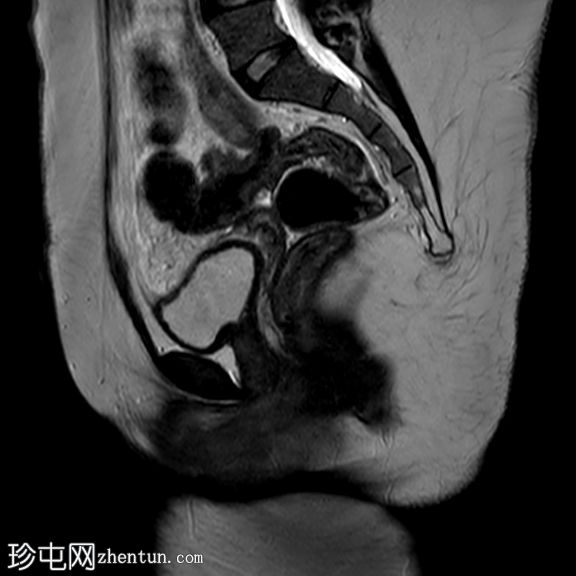

矢状位

T2加权像

盆腔两侧可见两个残角,位于双侧卵巢尾侧。可见一条水平带连接两个残角。左侧残角呈腔状,右侧残角呈非腔状。

可见宫颈阴道发育不全,从两个残角延伸出少量发育不良的宫颈组织带。

双侧卵巢功能正常,可见卵泡。

本病例展示了一种 Mayer-Rokitansky-Küster-Hauser 综合征 (MRKH),其特征为子宫缺失和双侧残角;左侧子宫角呈腔状,右侧子宫角呈非腔状。子宫角位于盆腔两侧,双侧卵巢尾侧,并由一条水平带连接。该病伴有宫颈阴道发育不全。

MRKH 患者常常被误认为完全没有子宫。有时,患者存在残角,残角内可见管腔内积血或子宫腺肌症,提示子宫内膜功能尚存。